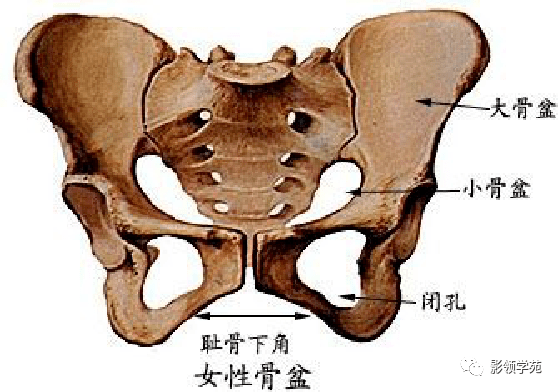

骨骼系统

骨骼系统